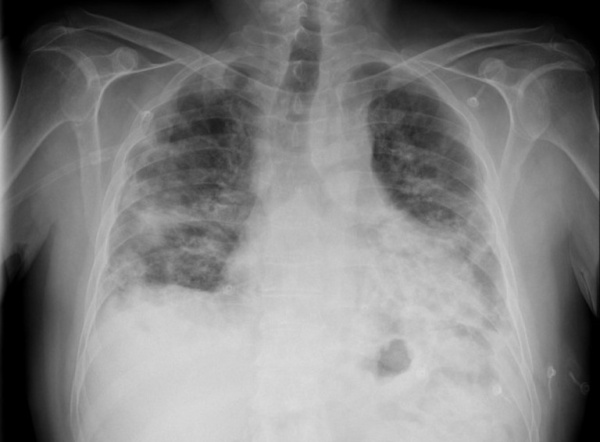

Считает себя больной с 14 июня, когда после переохлаждения отметила озноб, повышение температуры до 38°С, лечилась симптоматическими средствами, 24.06.10 г. - выполнена рентгенография органов грудной клетки, диагностирована сегментарная пневмония в нижней доле справа, назначена антибактериальная терапия (цефтазидим 2,0 г/сут в/м, левофлоксацин 0,5 г/сут per os). Лечение продолжалось 10 дней, на этом фоне температура снизилась до субфебрильной. Кашля, выделения мокроты не наблюдалось. 06.07.10 г. - при контрольном рентгенологическом исследовании выявлена отрицательная динамика с распространением инфильтрации на нижние отделы левого легкого.

При рентгенографии органов грудной клетки выявляются двусторонние диффузные периферические альвеолярные затемнения при нормальных объемах легких; могут также встречаться периферические затемнения, характерные для хронической эозинофильной пневмонии Хроническая эозинофильная пневмония Хроническая эозинофильная пневмония (ХЭП) – заболевание неизвестной этиологии, которое характеризуется хроническим патологическим накоплением эозинофилов в легком. (См. также Обзор эозинофильных. Прочитайте дополнительные сведения . В редких случаях альвеолярные затемнения носят односторонний характер. Часто наблюдаются рецидивирующие и мигрирующие инфильтраты. В редких случаях в начале заболевания могут наблюдаться нерегулярные линейные или очаговые интерстициальные инфильтраты или «сотовое легкое».

При КТВР выявляется очаговая консолидация воздушных пространств (у 90% пациентов), затемнения по типу «матового стекла», узловые затемнения, утолщение стенок и расширение бронхов. Очаговые затемнения встречаются чаще в периферических отделах нижних долей легких. КТВР позволяет обнаружить более обширные зоны поражения, нежели ожидается по результатам рентгенографии органов грудной клетки.

- Рентгенография легких. При изучении рентгенограммы отмечаются очаги поражения в легочной ткани по типу инфильтратов, сетчатых изменений, ограниченного уплотнения и фиброза. Рентгенологические находки соответствуют вышеназванным формам криптогенной пневмонии.

- КТ легких. Более чувствительный метод диагностики необходим для выявления мелких инфильтратов, которые не видны на рентгенограммах. В 20% случаев определяется обратный гало-признак – очаг «матового стекла, окруженный венчиком периферической консолидации. Изредка на КТ обнаруживают бронхоэктазию.